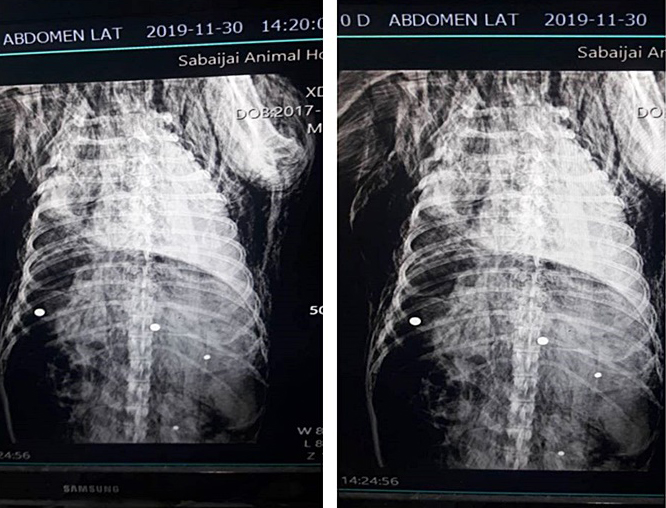

ทั้งนี้ จากการตรวจสอบพบว่า กระสุนที่ใช้ก่อเหตุเป็นกระสุนลูกปรายใหญ่ น่าจะเป็นลูกเหล็กที่ดึงเอามาจากตลับลูกปืนล้อรถยนต์ ใช้สำหรับยิงสัตว์ใหญ่

เพื่อนำส่งผ่าพิสูจน์หากระสุนฝังใน